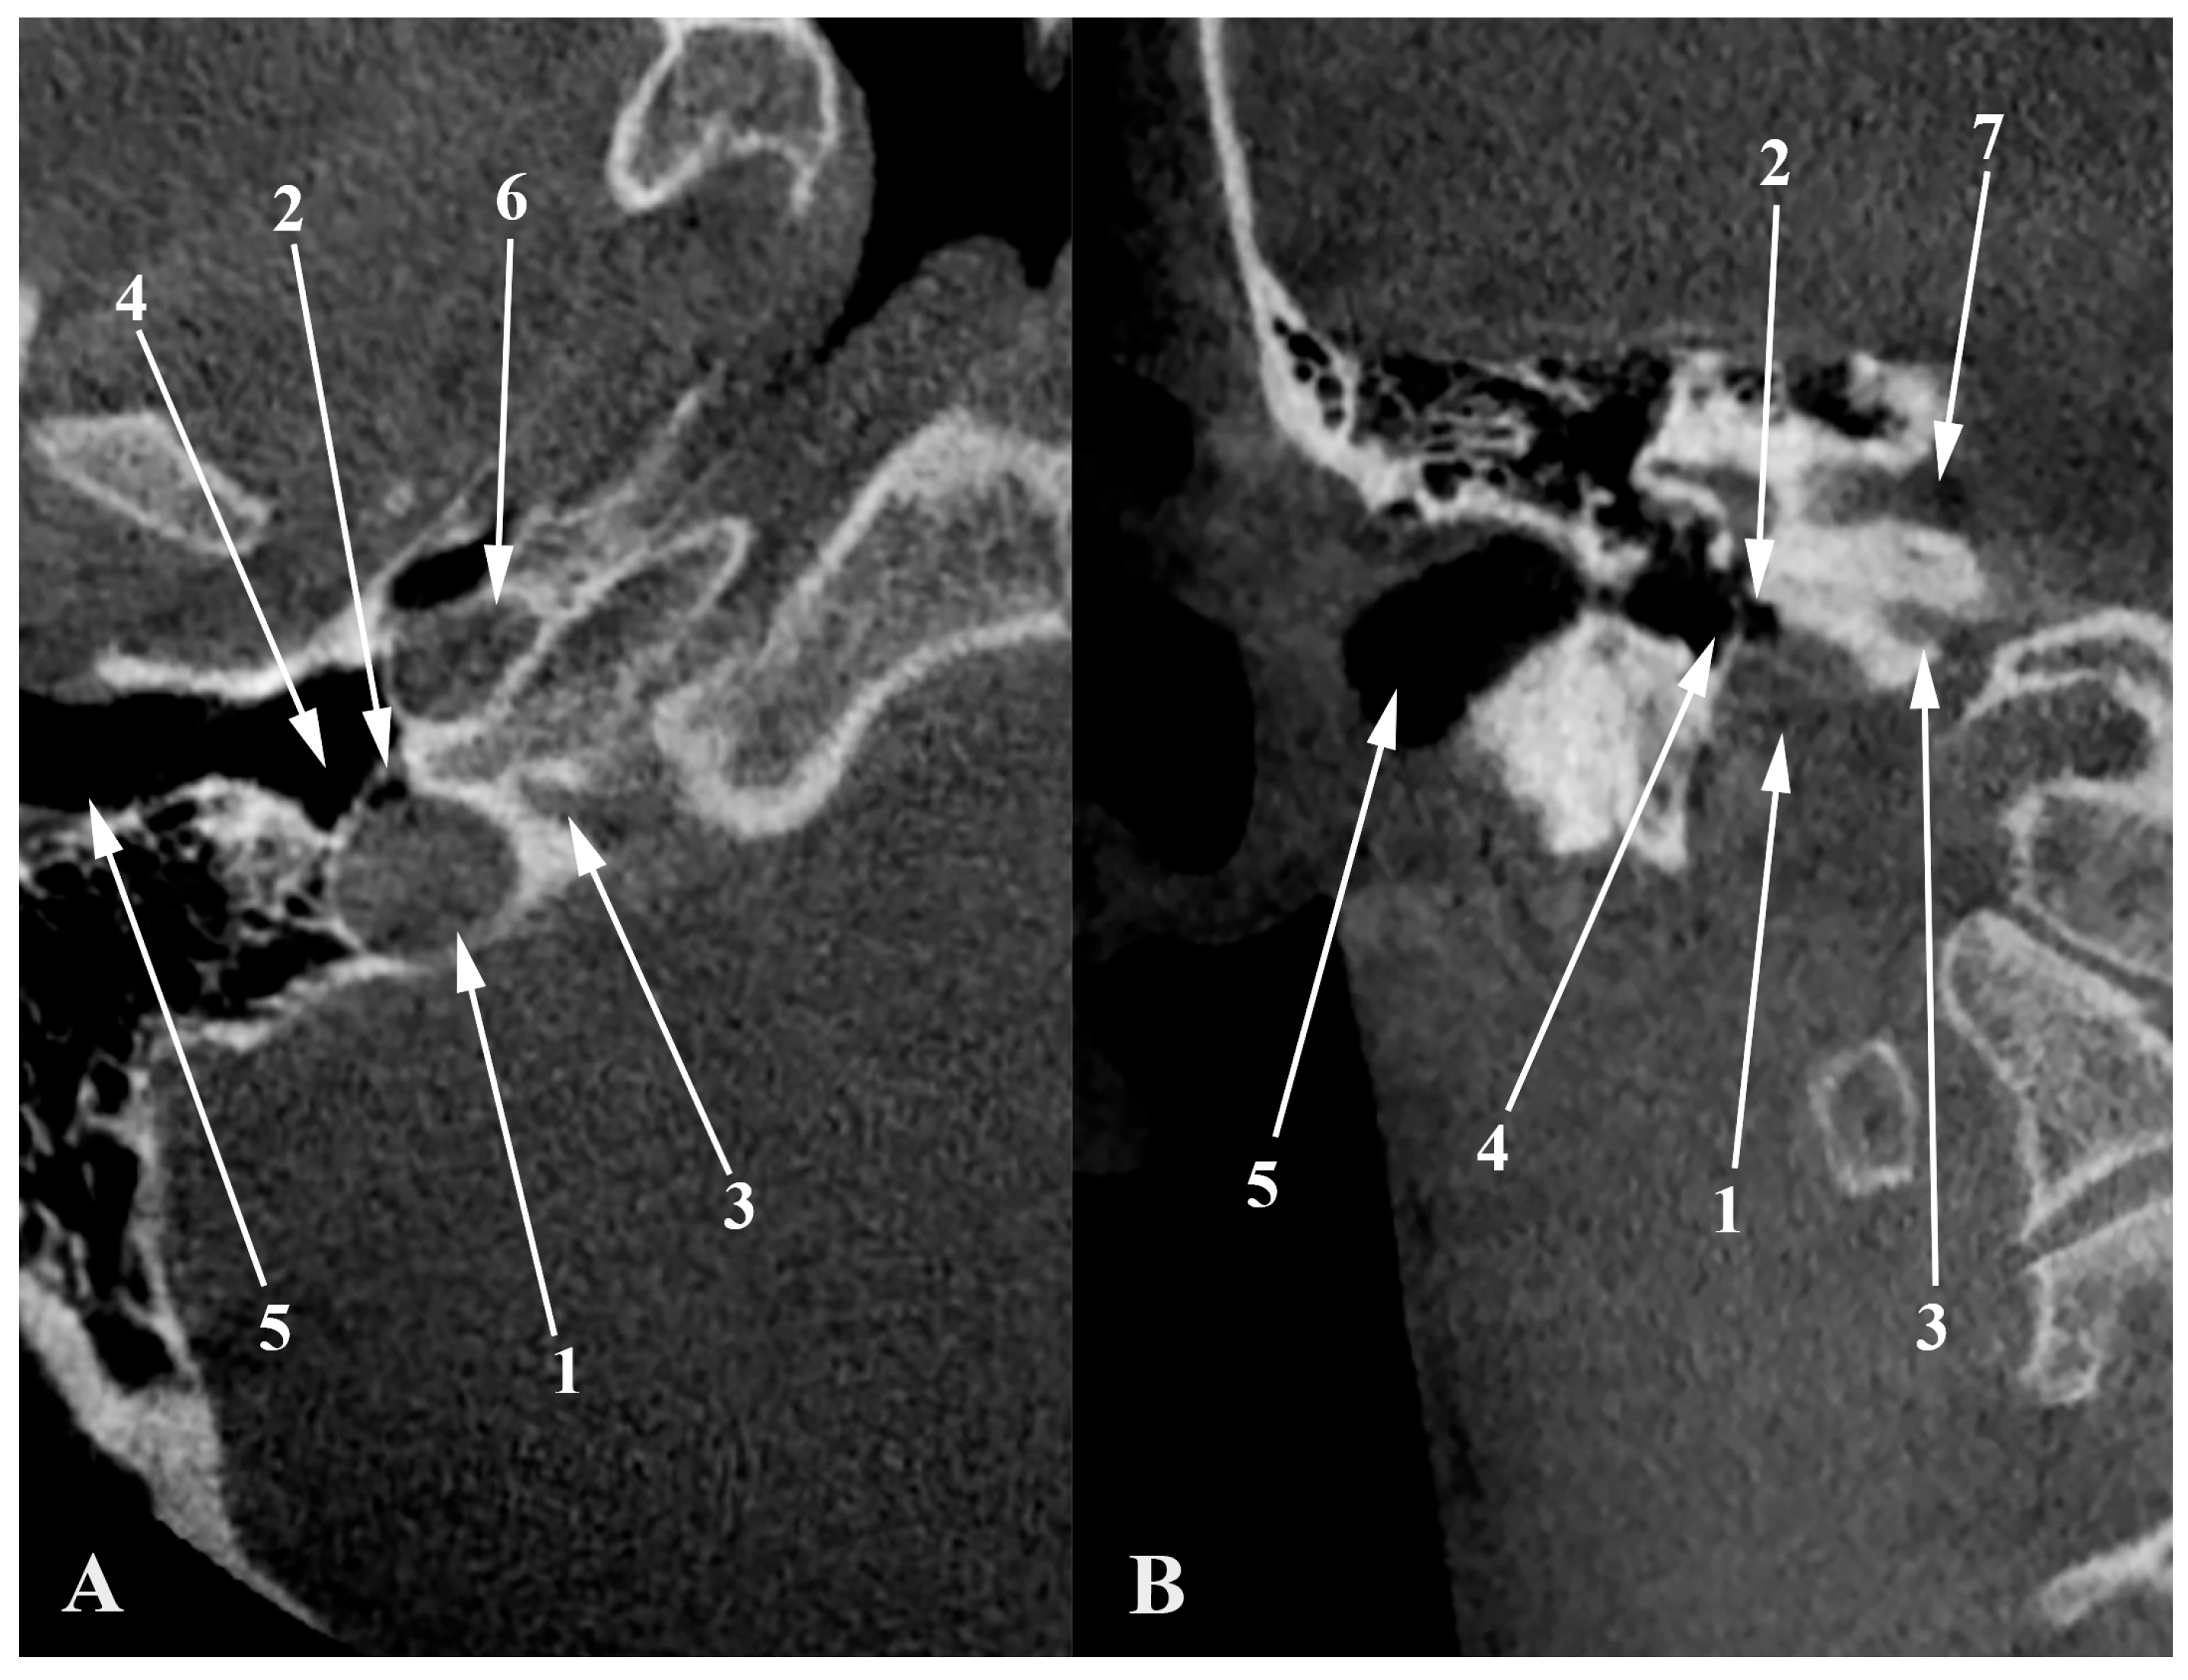

3. Diverticula

The “Condylar Jugular Diverticulum”: True or False?

4. High Jugular Bulb

5. Dehiscent Jugular Bulb